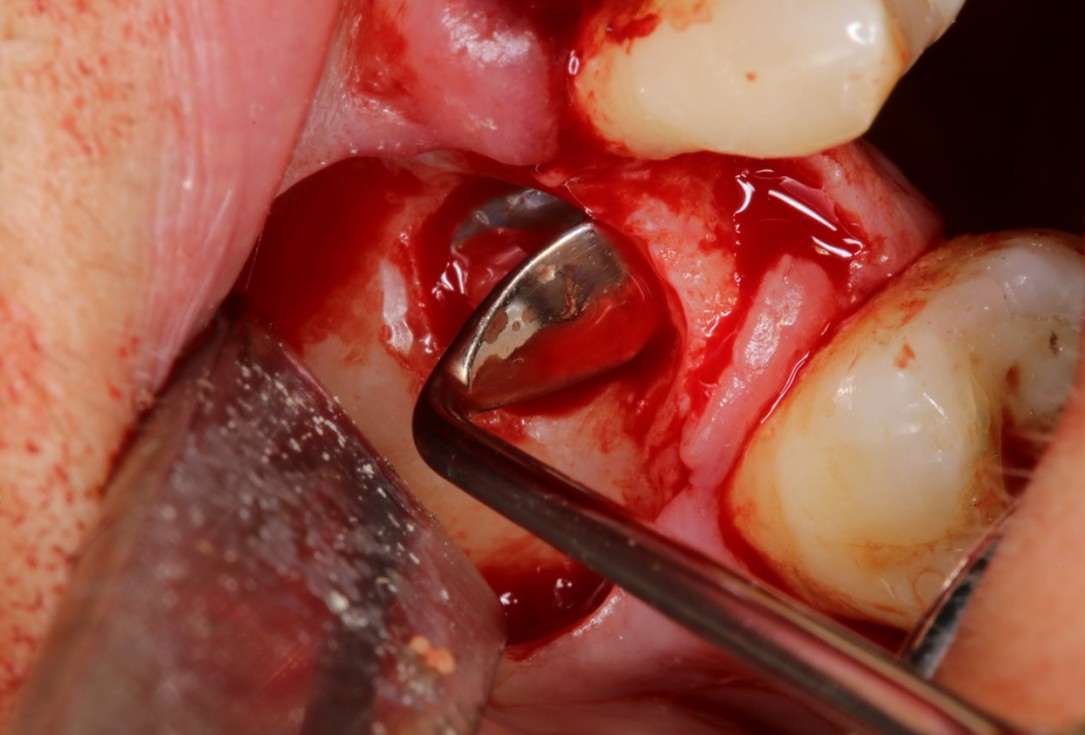

Periimplantitis treatment with maxgraft® bonering - Dr. B. Giesenhagen

Severe periimplantitis at tooth 15 with bone loss up to 1/3 of the implant